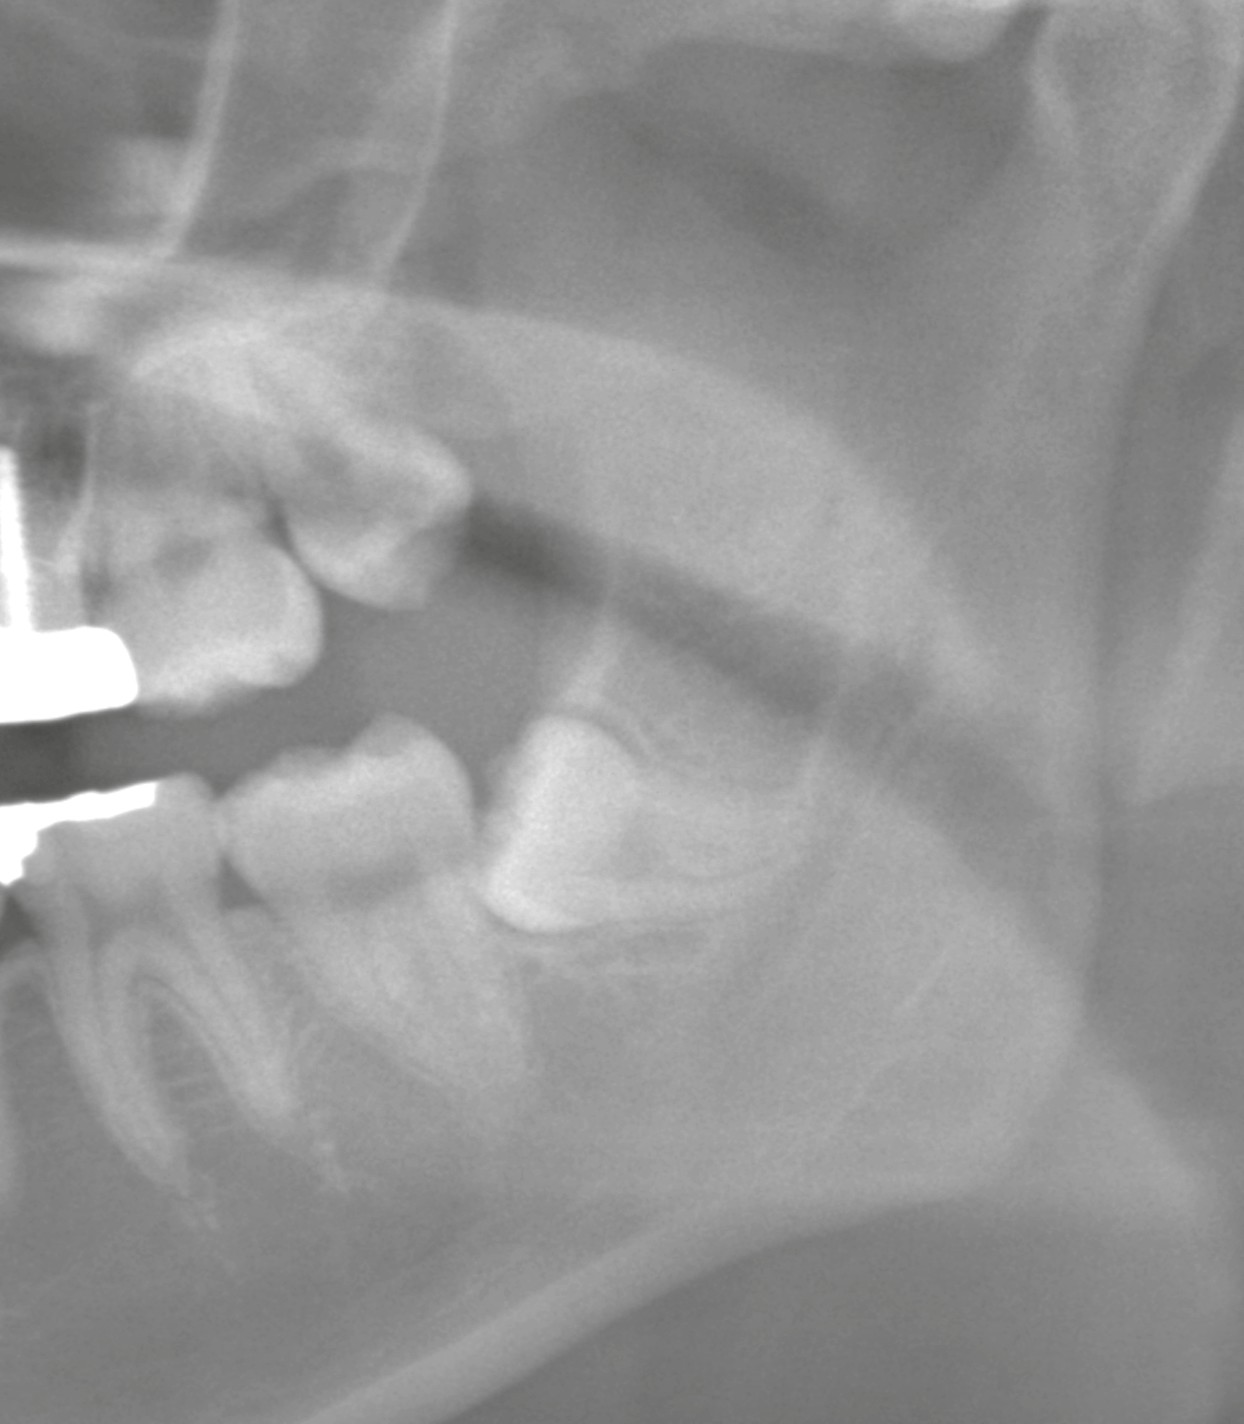

左下の親知らず

* 歯肉切開しオープンに

* 引っかかっていた歯冠を分割

* 一塊で撤去

* 事前のCTで下歯槽神経との位置関係を確認。近接はあるが触れておらず、神経障害のリスクは回避